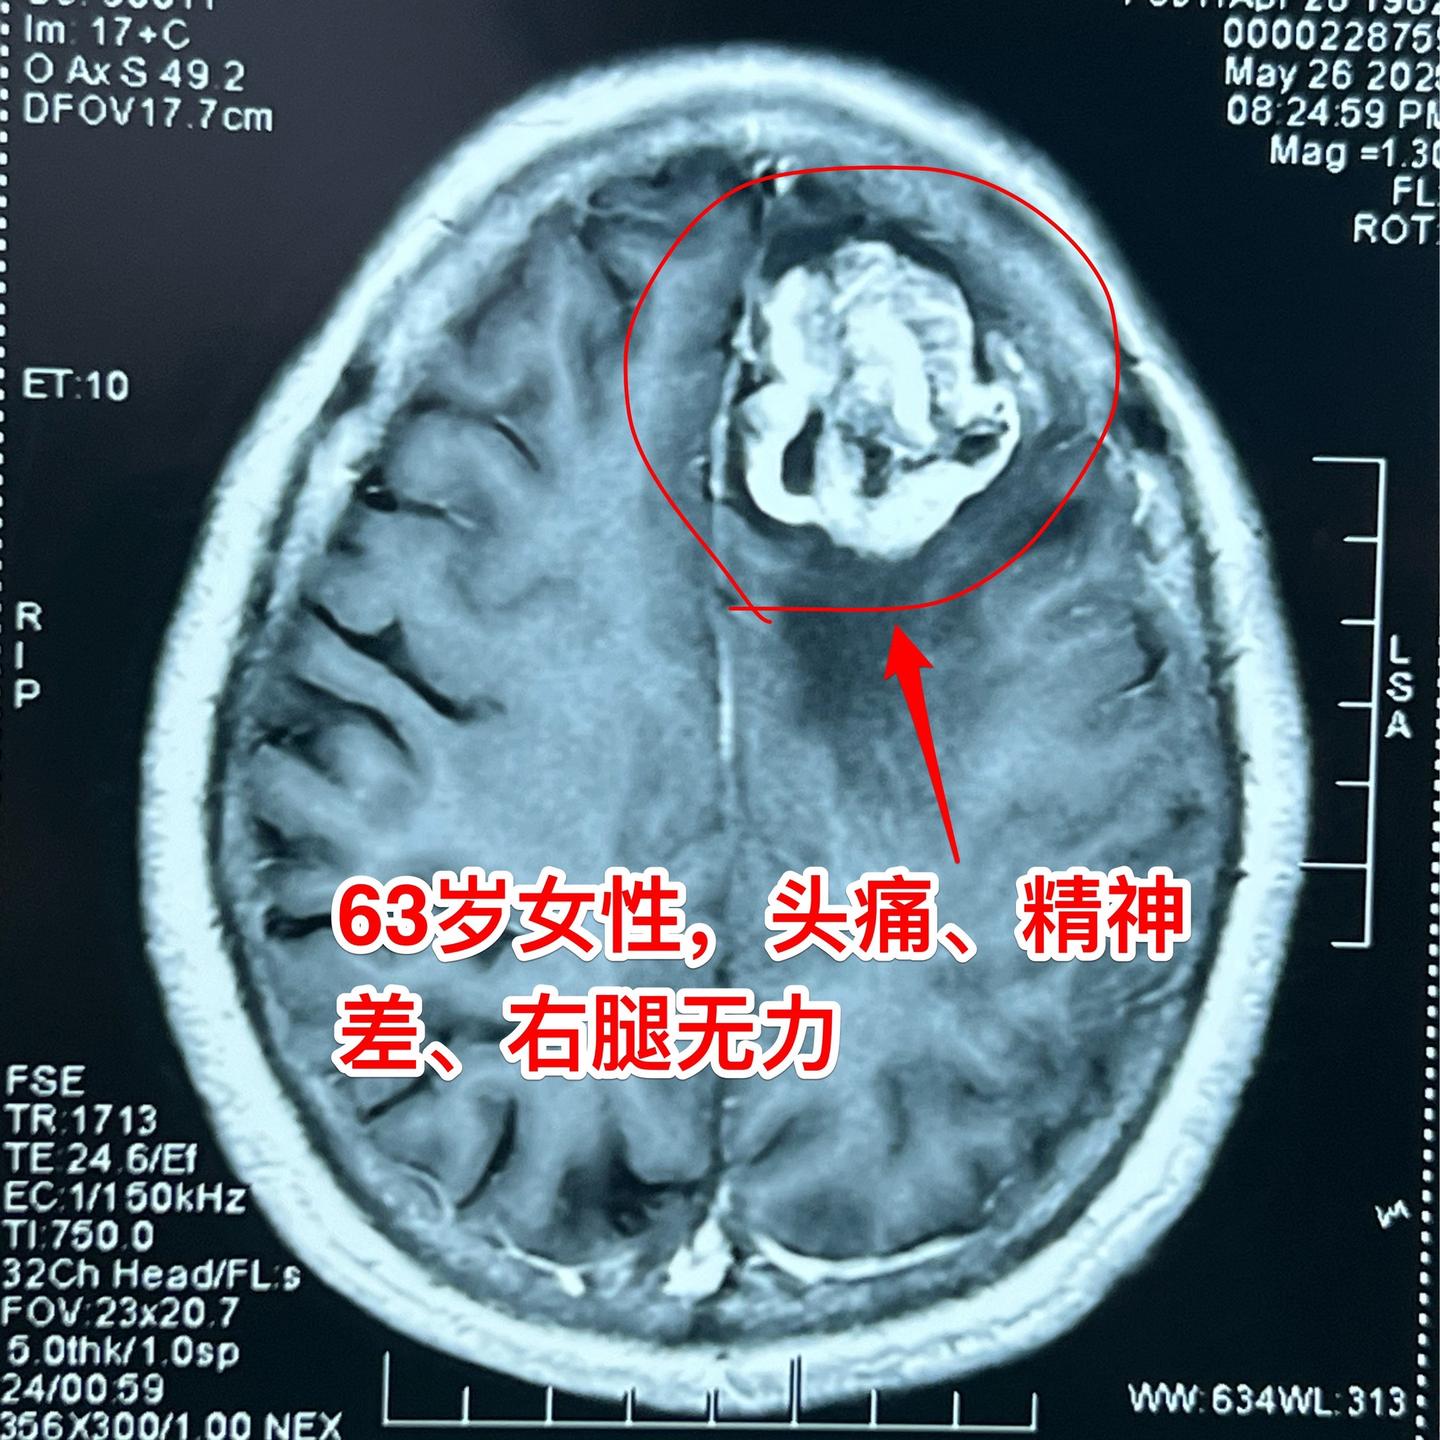

患冠心病、脑梗塞后又发现脑肿瘤。63岁随州女性,之前曾经患冠心病,作过心脏搭桥手术。也曾患过脑梗塞。幸运的是经过治疗,她没有明显的后遗症,可以在家做家务,还能下地干农活儿。 大约2周前病人出现头痛、精神差,随后出现右腿无力,行走时摔了一跤,病情越来越严重。 磁共振显示左侧额部有一个肿瘤,肿瘤周围有大面积水肿,胶质瘤?或者是别的肿瘤? 昨晚(5.30)为她作了手术,肿瘤得到整块切除。病人在手术后四肢活动无障碍。三个工作日后病理结果会出来的,后续的治疗需要根据病理诊